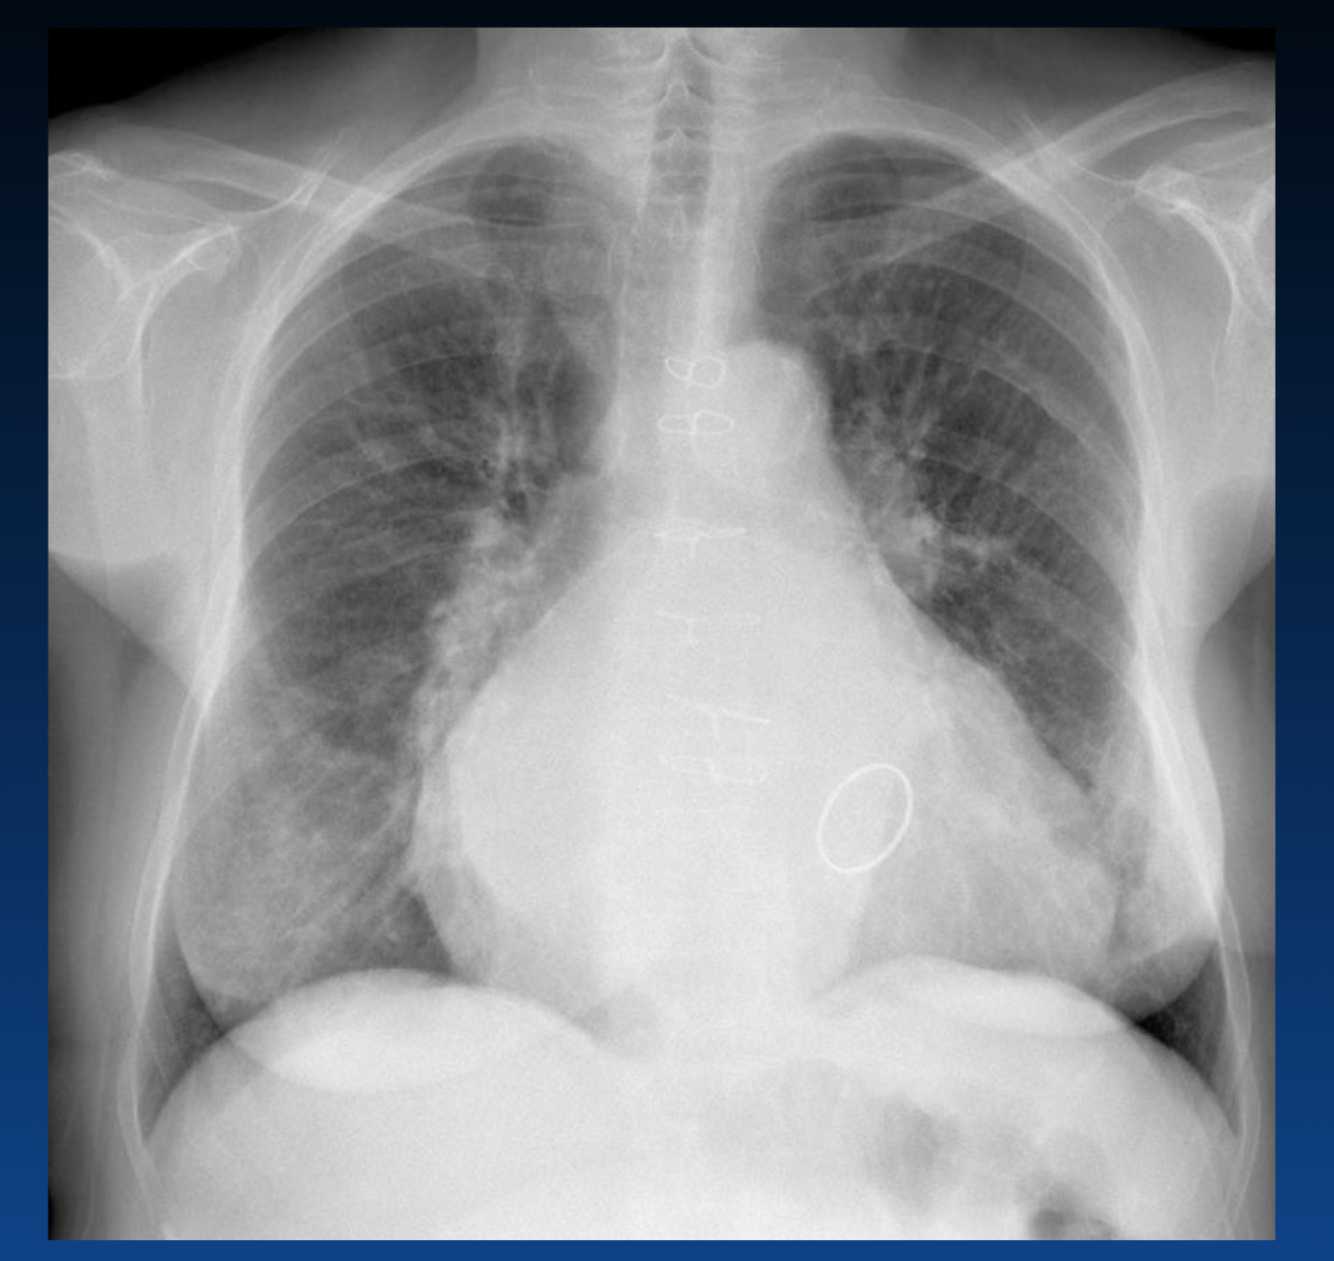

What are the reasons for increased CTR?

What is the Cardiothoracic Ratio?